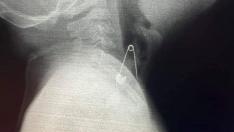

Министърът на здравеопазването проф.Костадин Ангелов ще обяви началото на работата на последно поколение компютърен томограф във варненската УМБАЛ “Света Марина” Събитието е насрочено за 11.00 часа, информират от здравното министерство.

С новата апаратура ще се разширят възможностите за диагностика на сърдечносъдовите и мозъчните заболявания, както и за изследване функцията на белия дроб.